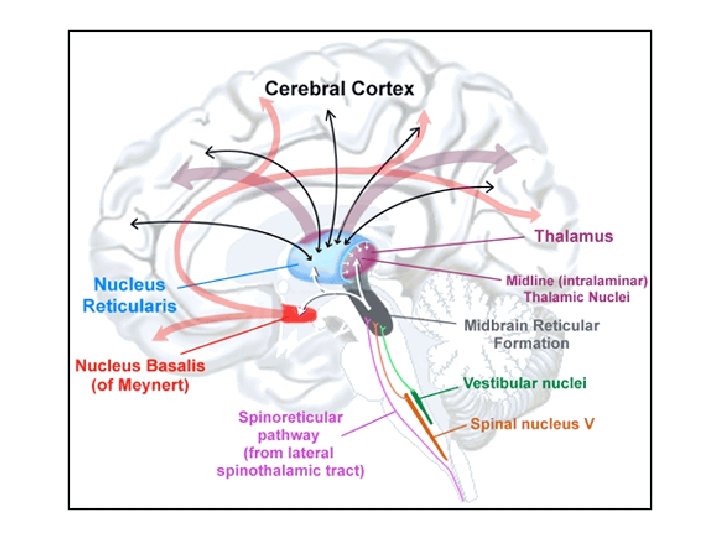

Basal Forebrain Syndromes • Anterior Communicating Artery (ACo. A) infarctions – prominent anterograde, variable retrograde amnesia – prominent confabulation – frontal extension of lesions • Basal forebrain and cholinergic projections to hippocampus

Basal Forebrain Anatomy